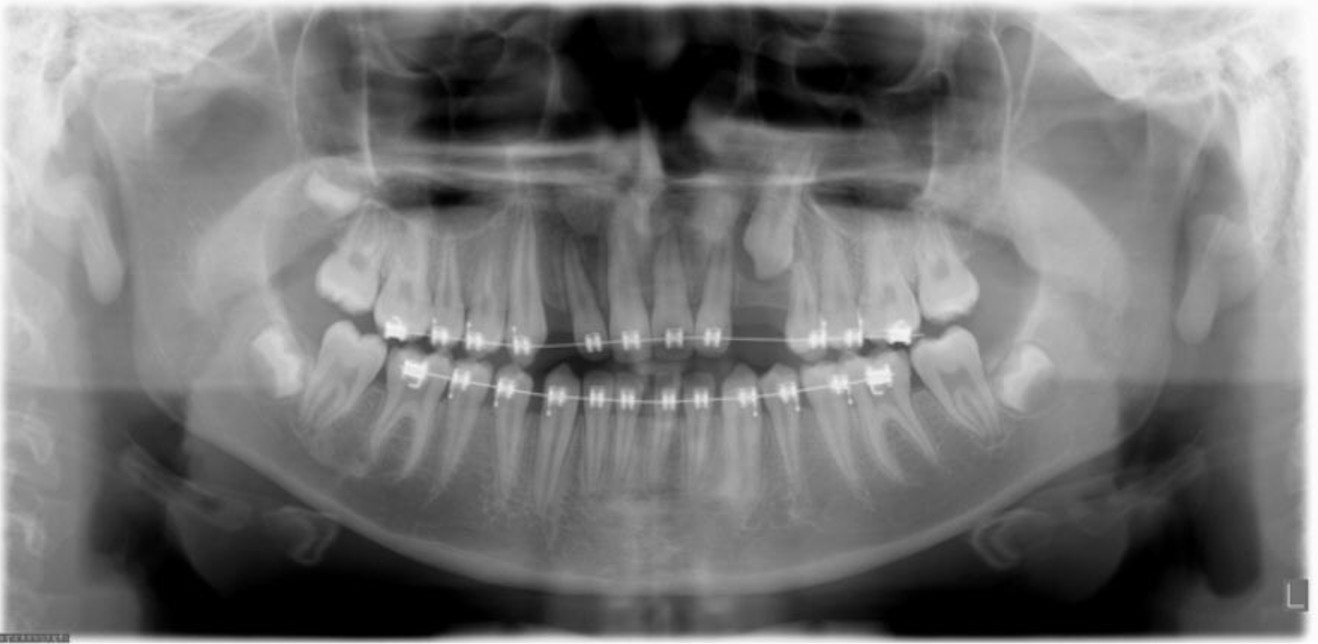

1. Root resorption (WHAT DOES THIS MEAN?!?!): The portion of the tooth that you see in your mouth is called the crown. The portion of the tooth located under the gums and embedded in the bone is called to root. Whenever we move teeth, we are placing forces on the roots so they can move through bone. This causes some trauma to the root. In rare cases, it may cause the root to shorten to a point where we must stop the treatment so it doesn’t get any worse. This is why we monitor the roots with “check up” x-rays every year. Catching the problem early prevents future problems of the roots becoming too short.

This picture is an x-ray of teeth and roots (this is the only way we can see if roots have gotten short). This is an example of a moderate case of root resorption. Once it happens, there is no treatment and must just be monitored throughout life (via x-rays).2. Gum disease/inflammation/periodontal disease: It is known that without proper oral hygiene, bacteria from plaque can cause swelling of the gums, gingivitis, and periodontal disease. Periodontal disease is a destruction of bone that surrounds the tooth. Without the proper amount of bone, the tooth doesn’t have as much support and over time can become loose or eventually be lost. Proper brushing and flossing during orthodontic treatment is essential to prevent these problems. It is harder to keep everything clean while wearing braces, so I would recommend adding an extra cleaning to your yearly schedule (normally you get 2 a year, but I would recommend 3 a year!)